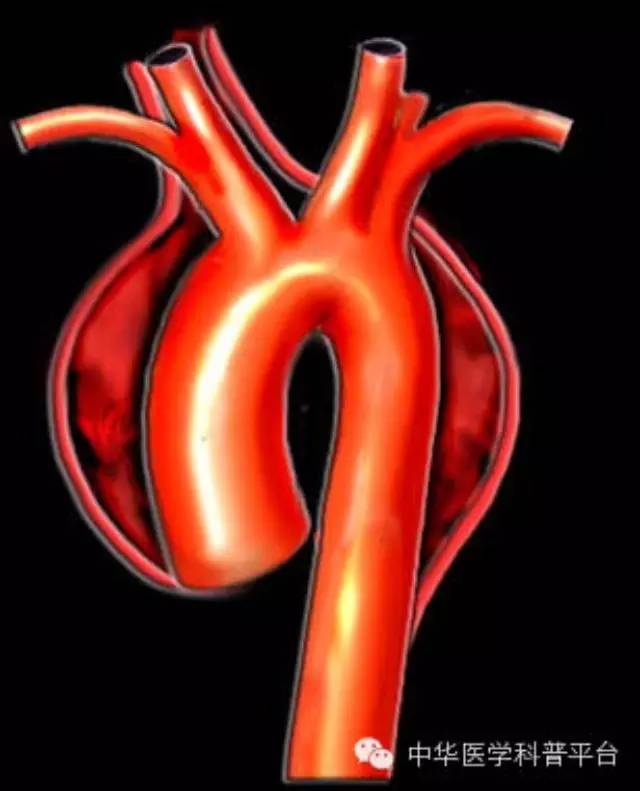

主动脉夹层是一种相对少见但极为严重的疾病,医学上将其定义为主动脉腔内的血液通过内膜的破口进人主动脉壁囊样变性的中层而形成夹层血肿,并沿着主动脉壁向周围延伸剥离的严重心血管急、危、重症。

【正常的人体动脉血管由3层结构组成,内膜、中膜和外膜,3层结构紧密贴合,共同承载血流的通过。主动脉夹层时血液通过主动脉内膜裂口,进入主动脉壁并造成正常动脉壁的分离。】